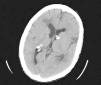

Mujer de 52 años con patrón intersticial pulmonary retraso mental profundo

52 year old woman with interstitial pulmonary pattern and severe mental retardation

TABLA 1. Criterios diagnósticos de la esclerosis tuberosa